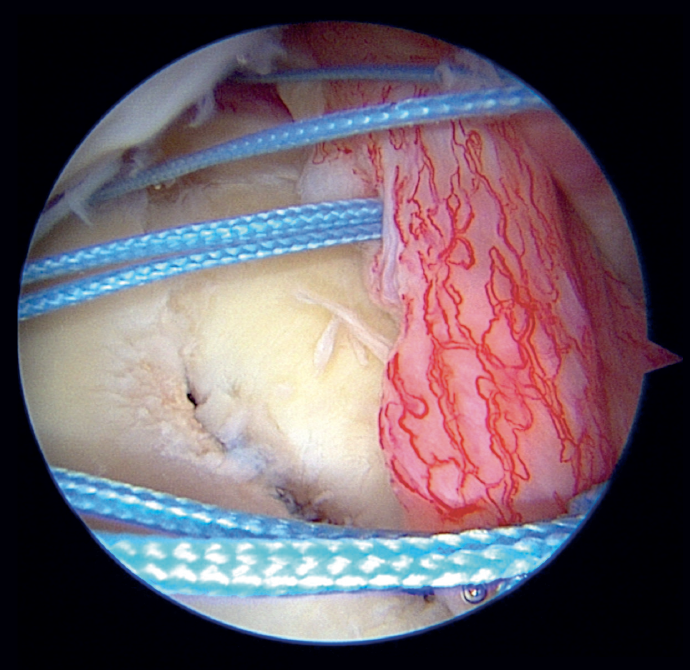

Direct trauma to the shoulder, with impacting of the humeral head in the glenoid cavity in some cases results in glenoid fracture and consequent glenohumeral dislocation. Glenoid bony lesions of this kind often evolve towards relapsing glenohumeral instability(1). When the size of the glenoid fracture proves relevant, with a classically established critical value of 20-25% of the area(2) and a currently defined value of 15% or more(3), surgery is the ideal treatment for avoiding the subsequent relapse of instability(4,5). Porcellini et al. in 2002(4) and Sugaya et al. in 2005(5) described the arthroscopic repair technique for lesions of this kind, consisting of reduction and block osteocapsular-ligamentous-labral fixation (Figure 1). Posteriorly, more sophisticated modifications of the technique were developed, such as the double-row / double pulley procedure of Ganokroj(6), consisting of a block reconstruction based on fixation at two different points: an anchoring medial with respect to the chondral margin of the glenoid cavity, and a lateral anchoring in the glenoid margin. Furthermore, other open and arthroscopic technical modifications have been described for such lesions(7).

In the classical Porcellini-Sugaya technique, debridement and roughening of the bone margins of the fracture was carried out with synoviotome, rasps and curettes (Figure 2). All-suture anchorings were used for the repair. The first anchoring was placed in the lowermost zone of the defect (Figure 3), and one its extremities extended to the damaged labrum in the lowermost zone, followed by knotting. The second anchoring was placed in the uppermost zone of the defect (Figure 4), in the same way as the first, followed by knotting. In those cases where considered necessary, one or two more anchorings were added proximal to the previous ones. Reduction and stability of the fragment was checked.